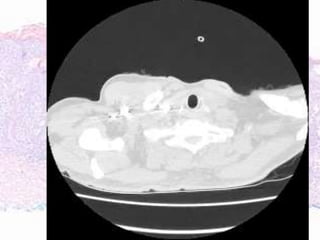

• PD identified September 2016

• Ipilimumab commenced October 2016 - x 4

doses